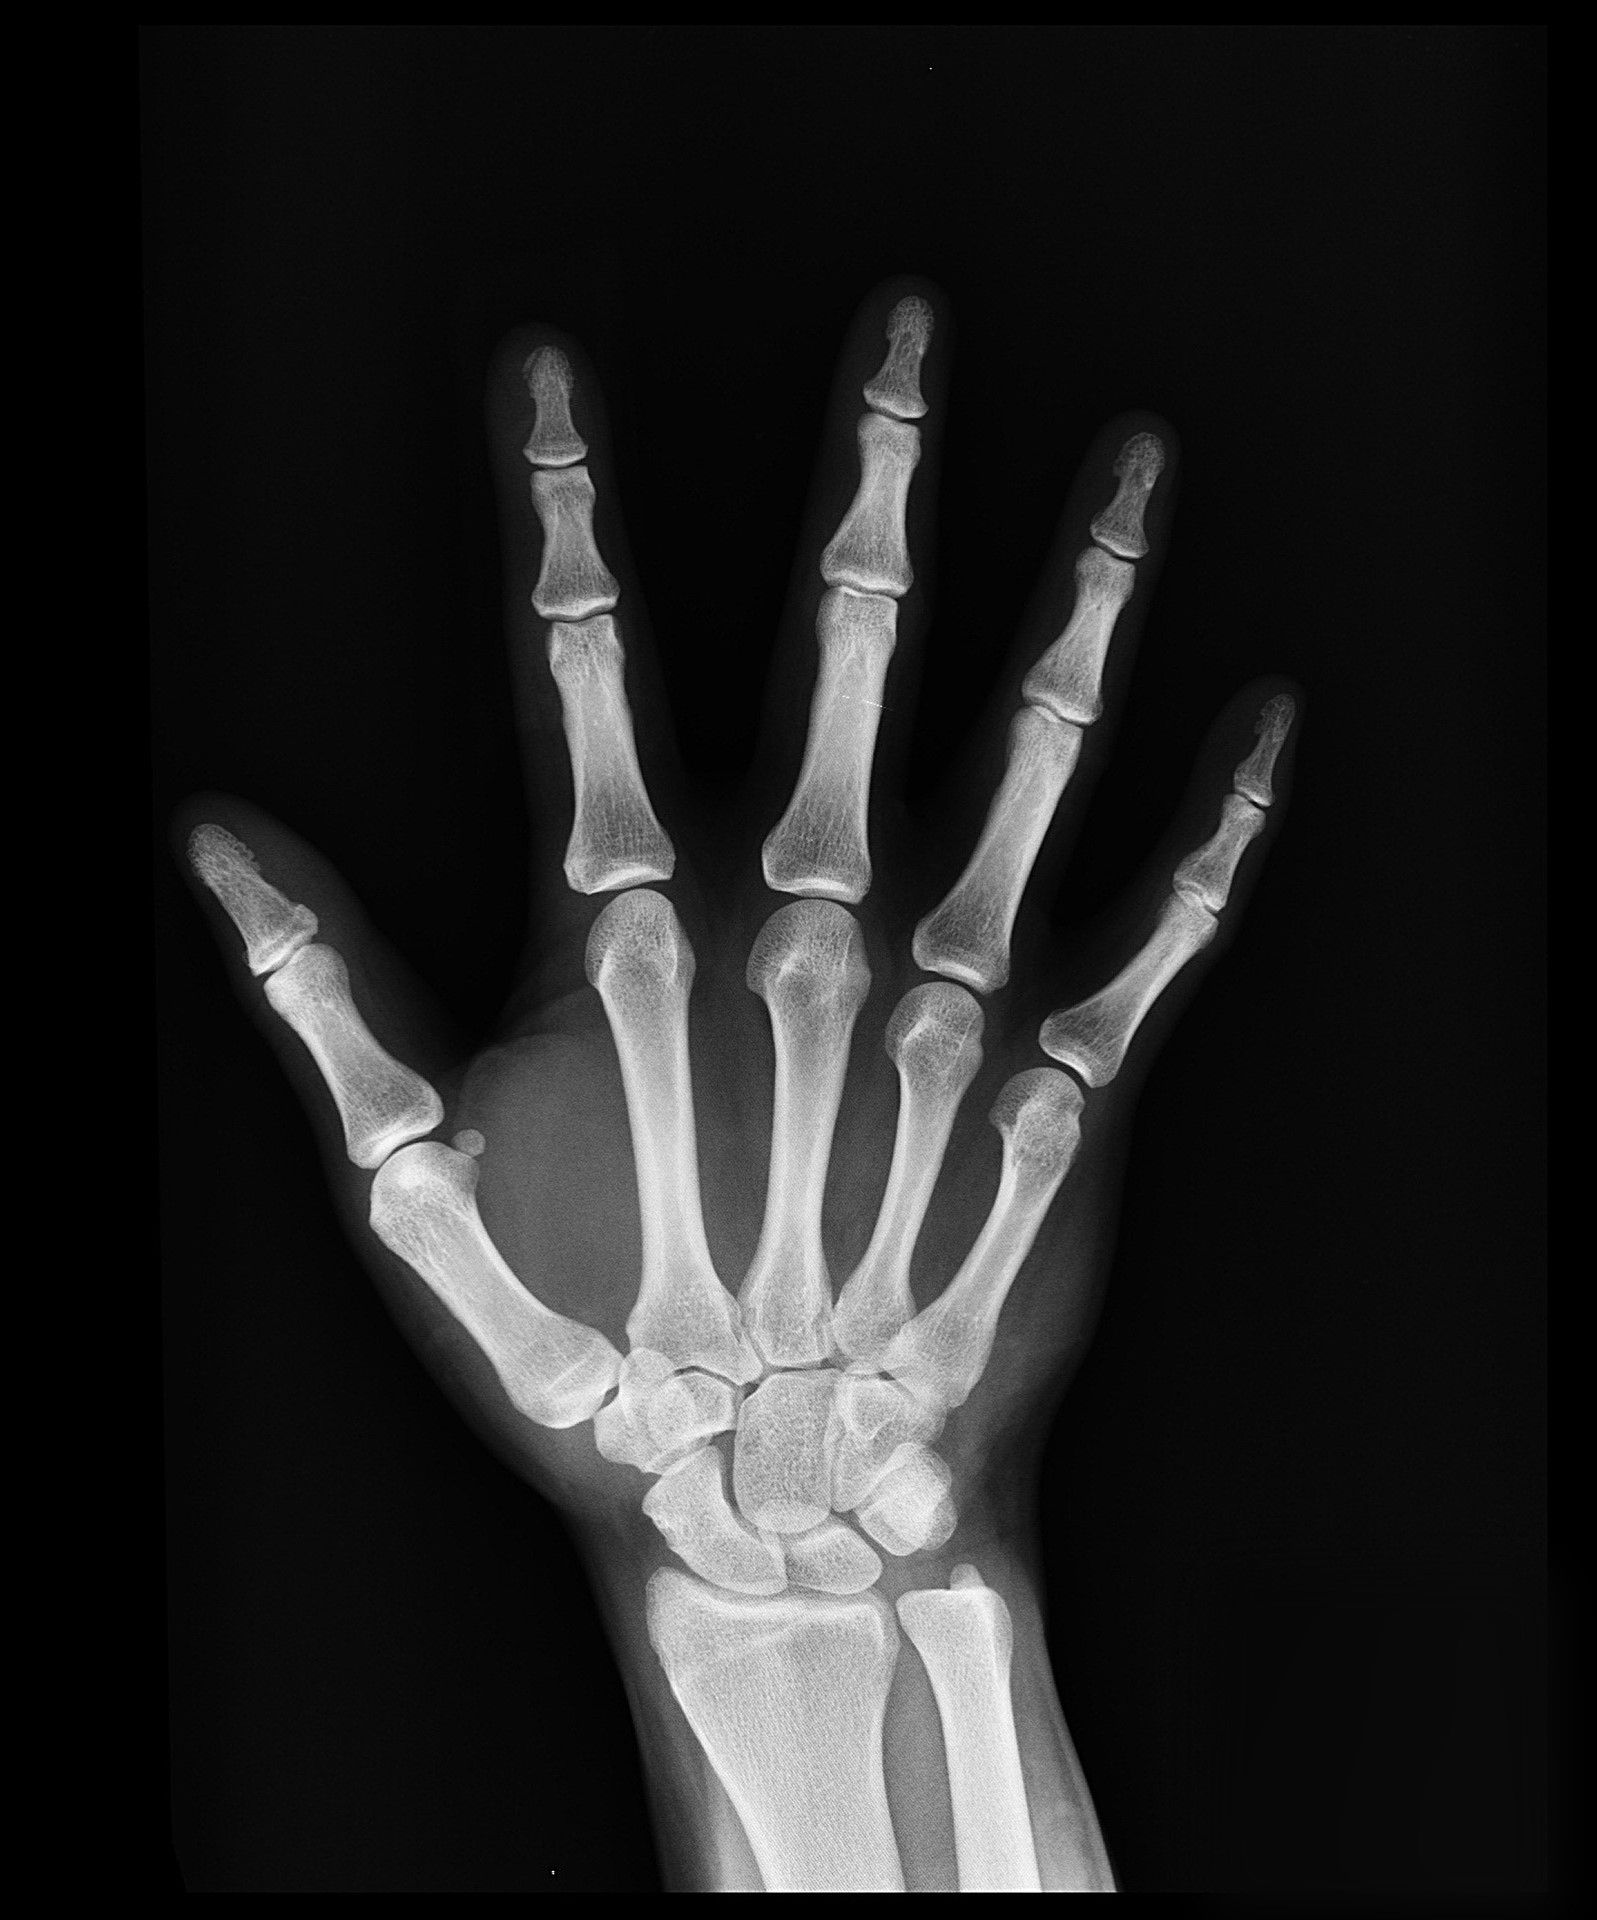

As you already know, what I didn't know yet, was that I was not okay. I had fractured my left hand, and a finger on my right hand besides. If it was left to me, I would have just applied an ice-pack or two and called it a day. But my mom insisted that I see our orthopedic doctor, who asked for the X-rays to be done, that eventually revealed my broken bones... and thank God she did, cuz otherwise I may have healed in some weird way.